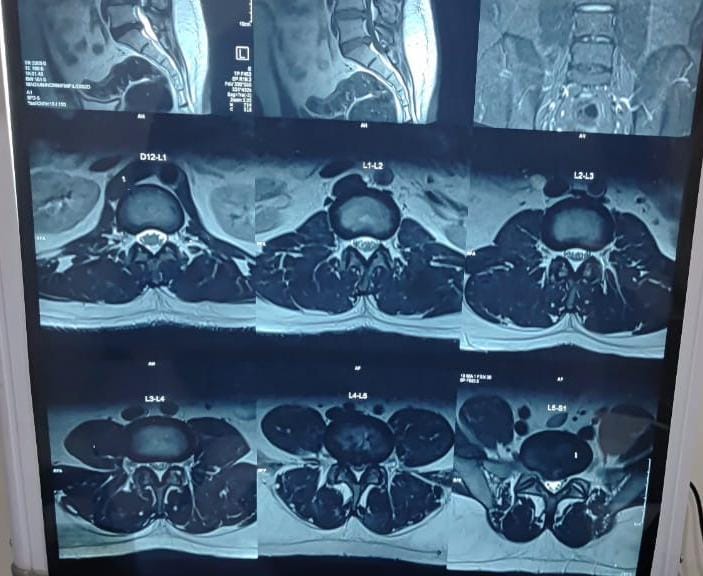

Sunshine Ortho Pain Superspeciality Hospital is the Best Multispeciality Hospital, Orthopedic Hospital in Wakad, Hnjewadi, PCMC and Pune. We are specialized in Orthopedic Surgeries, Robotic Joint Replacement Surgery, Hip and Knee Replacement Surgery, Complex Trauma And Pelvi Acetabular Surgery, Spine Surgery, Sports Medicine And Arthroscopy, Regenerative Therapy/Prolotherapy, Shoulder Surgery, Knee Surgeries, Foot And Ankle Treatment in Wakad, Hinjewadi, PCMC and Pune.